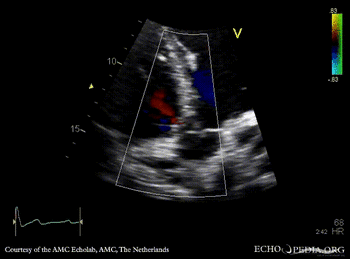

Perimembraneous VSD

E00682.jpg

PSAX with Color Doppler Continuous-wave Doppler signal of flow through ventricular septum defect